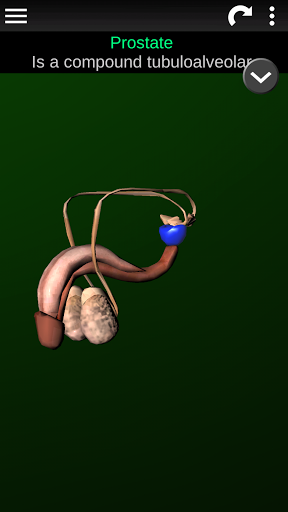

* Репродуктивна система, яка включає чоловічі та жіночі репродуктивні органи.

* Описи кожного органу.